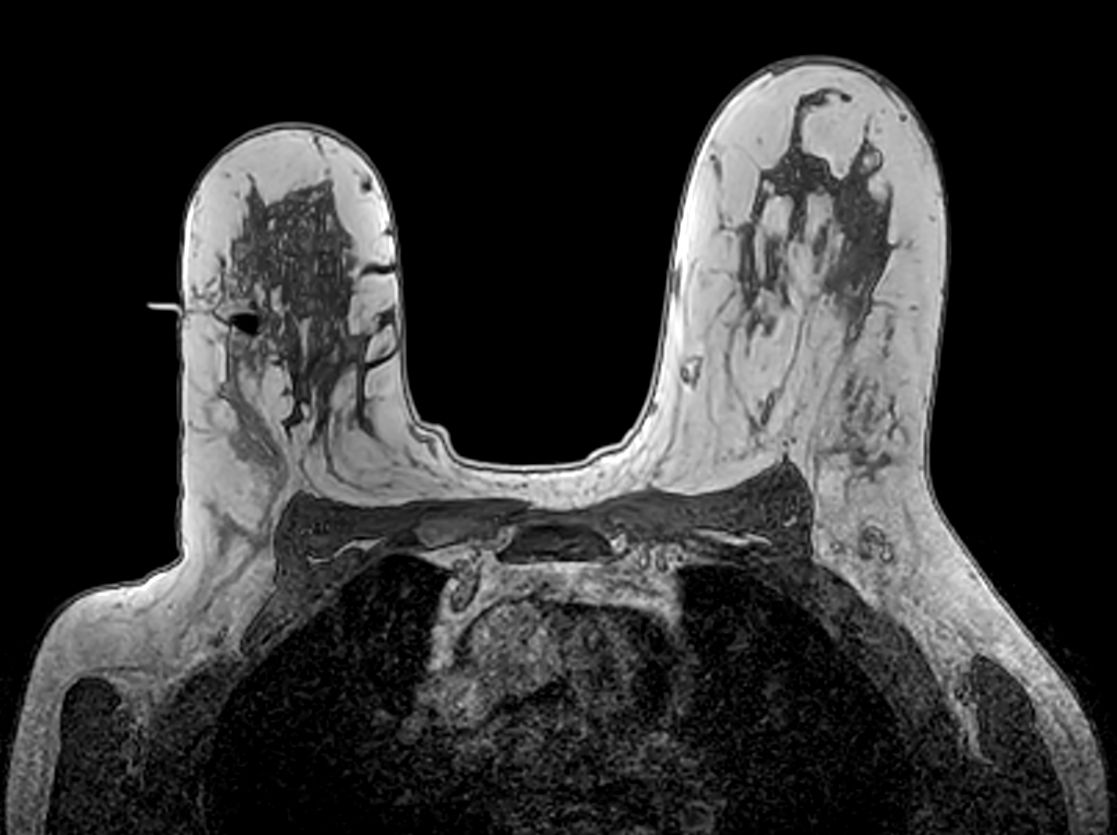

Axial 3D T1w FFE - Confirmation Fiducial marker positioning correct